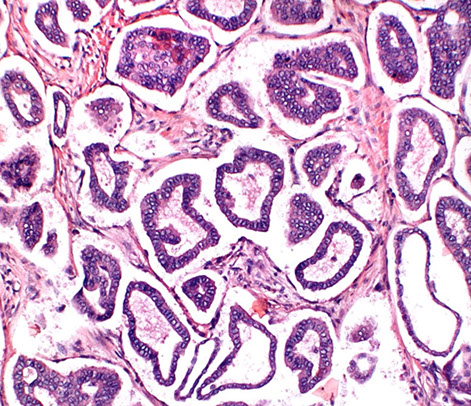

Cross section at the level of nipple shows lactiferous ducts with a scalloped appearance, possibly related to the origin of segmental branches. The duct system resembles any other dichotomously branching system of glands where a single large duct successively branches down to its most terminal level. The lactiferous duct gives rise to segmental ducts, which in turn gives rise to sub-segmental branches and so on until a terminal duct lobular unit is formed. The large lactiferous duct is the site for solitary papilloma and duct ectasia with nipple discharge.

As the lactiferous duct runs deeper into the breast tissue it branches out into segmental branches which are smaller but still lined by two layers (arrow): the luminal epithelial layer of cuboidal to columnar cells and an outer myoepithelial contractile layer.

This photomicrograph depicts a sub-segmental duct (arrow) giving rise to multiple “Terminal duct lobular units (arrowheads)” embedded in dense stroma. The TDLU are terminal units of the duct system.